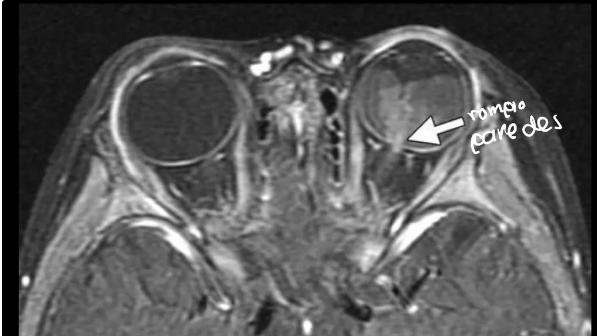

Que evalúa la RM en retinoblastoma

evalúa implicaciones intra y extraoculares asi como intracraneales- Identificación de hemorragia retinal y rompe paredes

¿De qué enfermedad sospechas?

Desprendimiento de retina

Que podemos ver en una RM y TC en desprendimiento de retina

Hipersensidad Fluido subretiniano Neoplasias